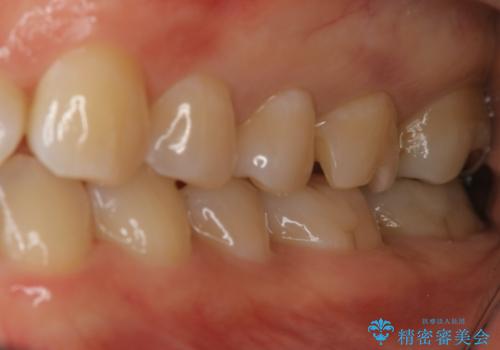

奥歯を白くしたい

- 左上6番の銀歯をセラミックにしたいと希望され来院された患者様です。

切削量を考慮し、セラミックインレーを選択しました。

銀歯を除去したところ虫歯が深かったので、CRを詰めた上で形態を整えています。